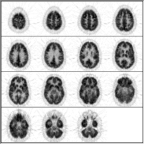

Neurological scans are normally presented with the right/left sides of the brain reversed with respect to the viewer. In an FDG-PET scan metabolism should be symmetrical from side-to-side.

Likewise, metabolism should be similar between the anterior and posterior regions of the brain.